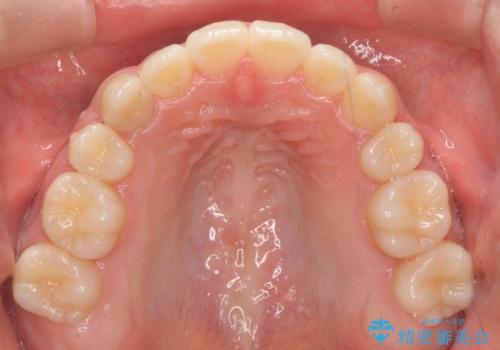

八重歯や、前歯のオープンバイト(開咬)の症状があり、マウスピース(インビザライン)矯正単独では治すのが難しい症状が複合していました。

八重歯や抜歯したスペースの閉鎖をワイヤー矯正で前半行い、治療後半は目立たないインビザラインでかみ合わせを調整しました。

ワイヤー矯正からインビザラインへの変更は、歯磨きも簡単になり、目立たず、さらにワイヤーと併用することで妥協せずしっかり治療結果も出すことができます。

上の奥歯を後ろ下げるために、矯正用ミニスクリューを使用しています。